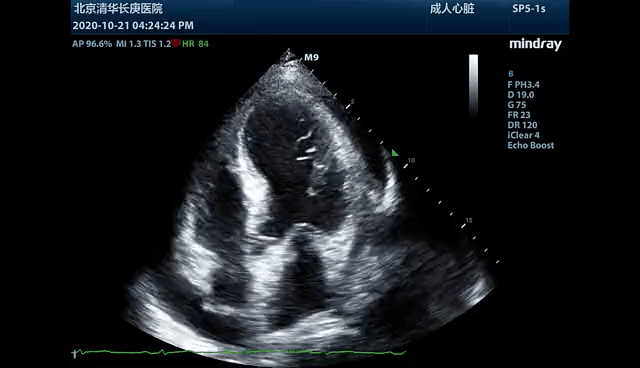

一例48岁男性心肌梗死患者,超声心动图发现并发心功能不全,大量心包积液